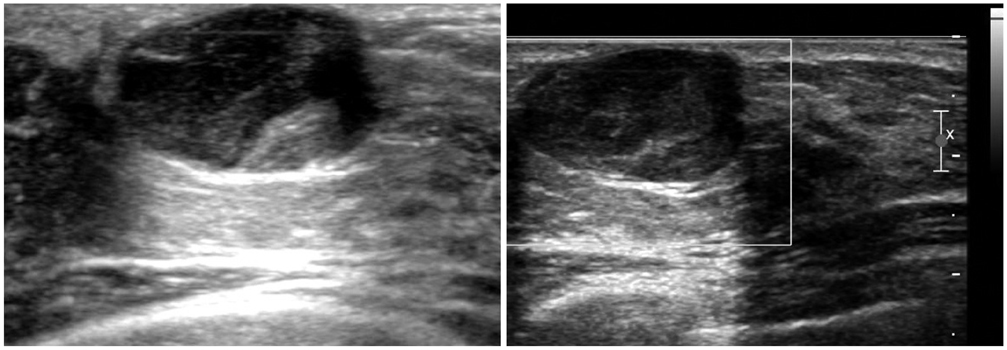

- The purpose of this study is to review various breast diseases in children and adolescents and to illustrate the sonographic findings. We reviewed the cases at our institution in order to identify breast disease in children and adolescent patients who underwent sonography and mammography. Breast disease in children and adolescents included developmental disturbance, infection, benign tumors and inherent defects. In contrast to adults, the radiologic findings of malignant breast conditions in pediatric populations have rarely been reported; however, we show ductal carcinoma in situ with juvenile fibroadenoma and rhabdomyosarcoma. During childhood and adolescence, the recognition and correct identification of physiologic breast development and specific lesions in breast entities on radiologic findings is most helpful in identifying and characterizing abnormalities and in guiding further investigation.